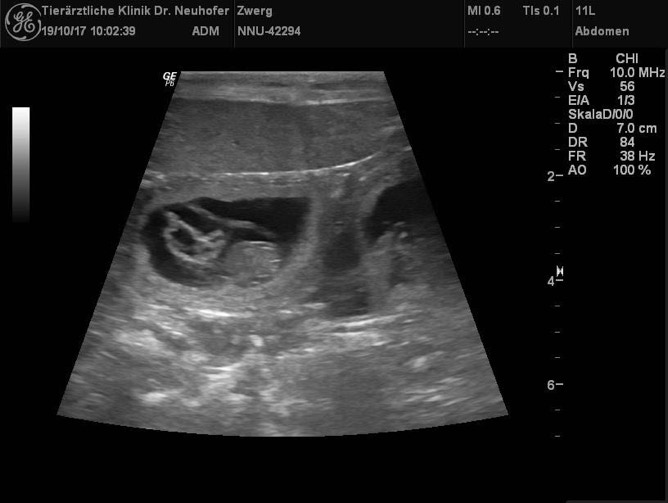

Wir waren am 19.10 mit Shirley beim Tierarzt zum Ultraschall. Sie ist tragend!!!

Shirley erwartet um den 22.11.17 süße Miniature Australian Shepherd Welpen.